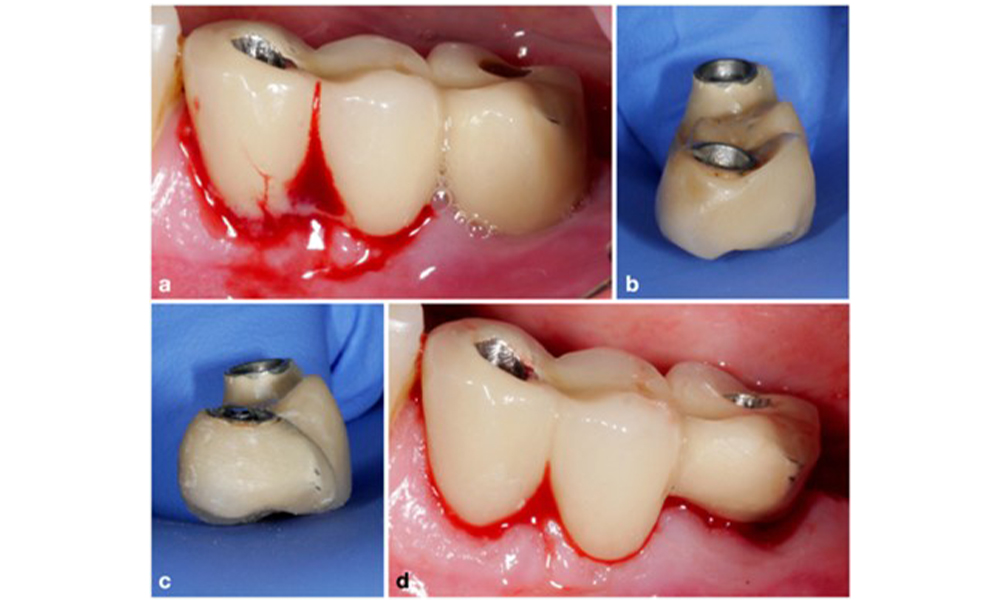

Management of peri-implantitis at implants judged as treatable consists of a non-surgical phase, which is often followed by surgical intervention. For the non-surgical approach, similar measures as those applied for the treatment of peri-implant mucositis are used; based on laboratory experiments air-polishing devices with a subgingival nozzle appear to provide certain advantages in terms of biofilm removal, compared to hand- or ultrasonic instruments (Herrera et al. 2023; Moharrami et al. 2019; Ronay et al. 2017) (figure 9).

Patient case with peri-implantitis. The non-surgical treatment is performed by using the supragingival (a-b) and subgingival handpiece of an air-polishing device (c-d). Removing the supra-construction provides better access to the implant surface (d).

Figure 9. Patient case with peri-implantitis. The non-surgical treatment is performed by using the supragingival (a-b) and subgingival handpiece of an air-polishing device (c-d). Removing the supra-construction provides better access to the implant surface (d).